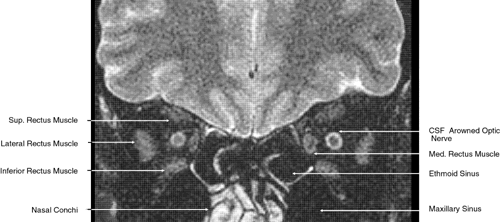

The globe is shown in Figure 12. The orbit and periorbital structures are shown in Figures 13 through 16, and the optic canal is shown in Figures 17 through 26. The cavernous sinus and optic chiasm are shown in Figures 27 and 28, and the posterior visual pathway and cranial nerves are shown in Figures 29 through 33.

Fig. 19. Coronal images through midorbit posterior to the globe. A. Computed tomography scan.B. T1-weighted magnetic resonance imaging.

Fig. 20. Coronal images through orbital apex. A. Computed tomography scan. B. T1-weighted magnetic resonance imaging. C. Anatomic section of a cadaver head at the level of the orbital apex.